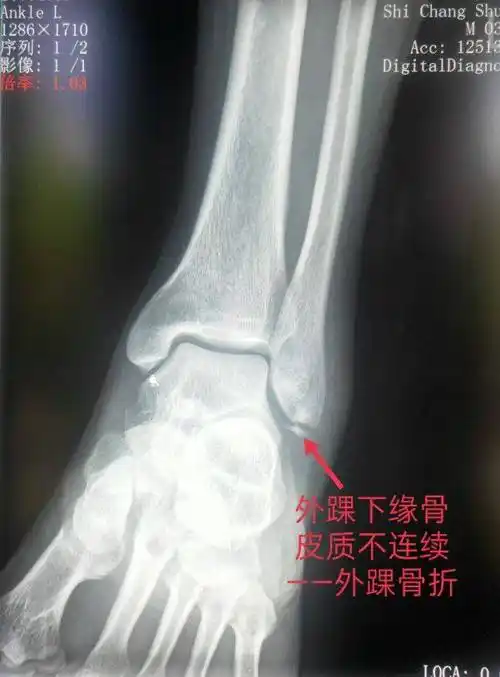

踝关节骨折不是打石膏那么简单

组成踝关节的骨踝关节俗称"脚踝",由胫骨,腓骨和距骨构成,胫骨和腓骨